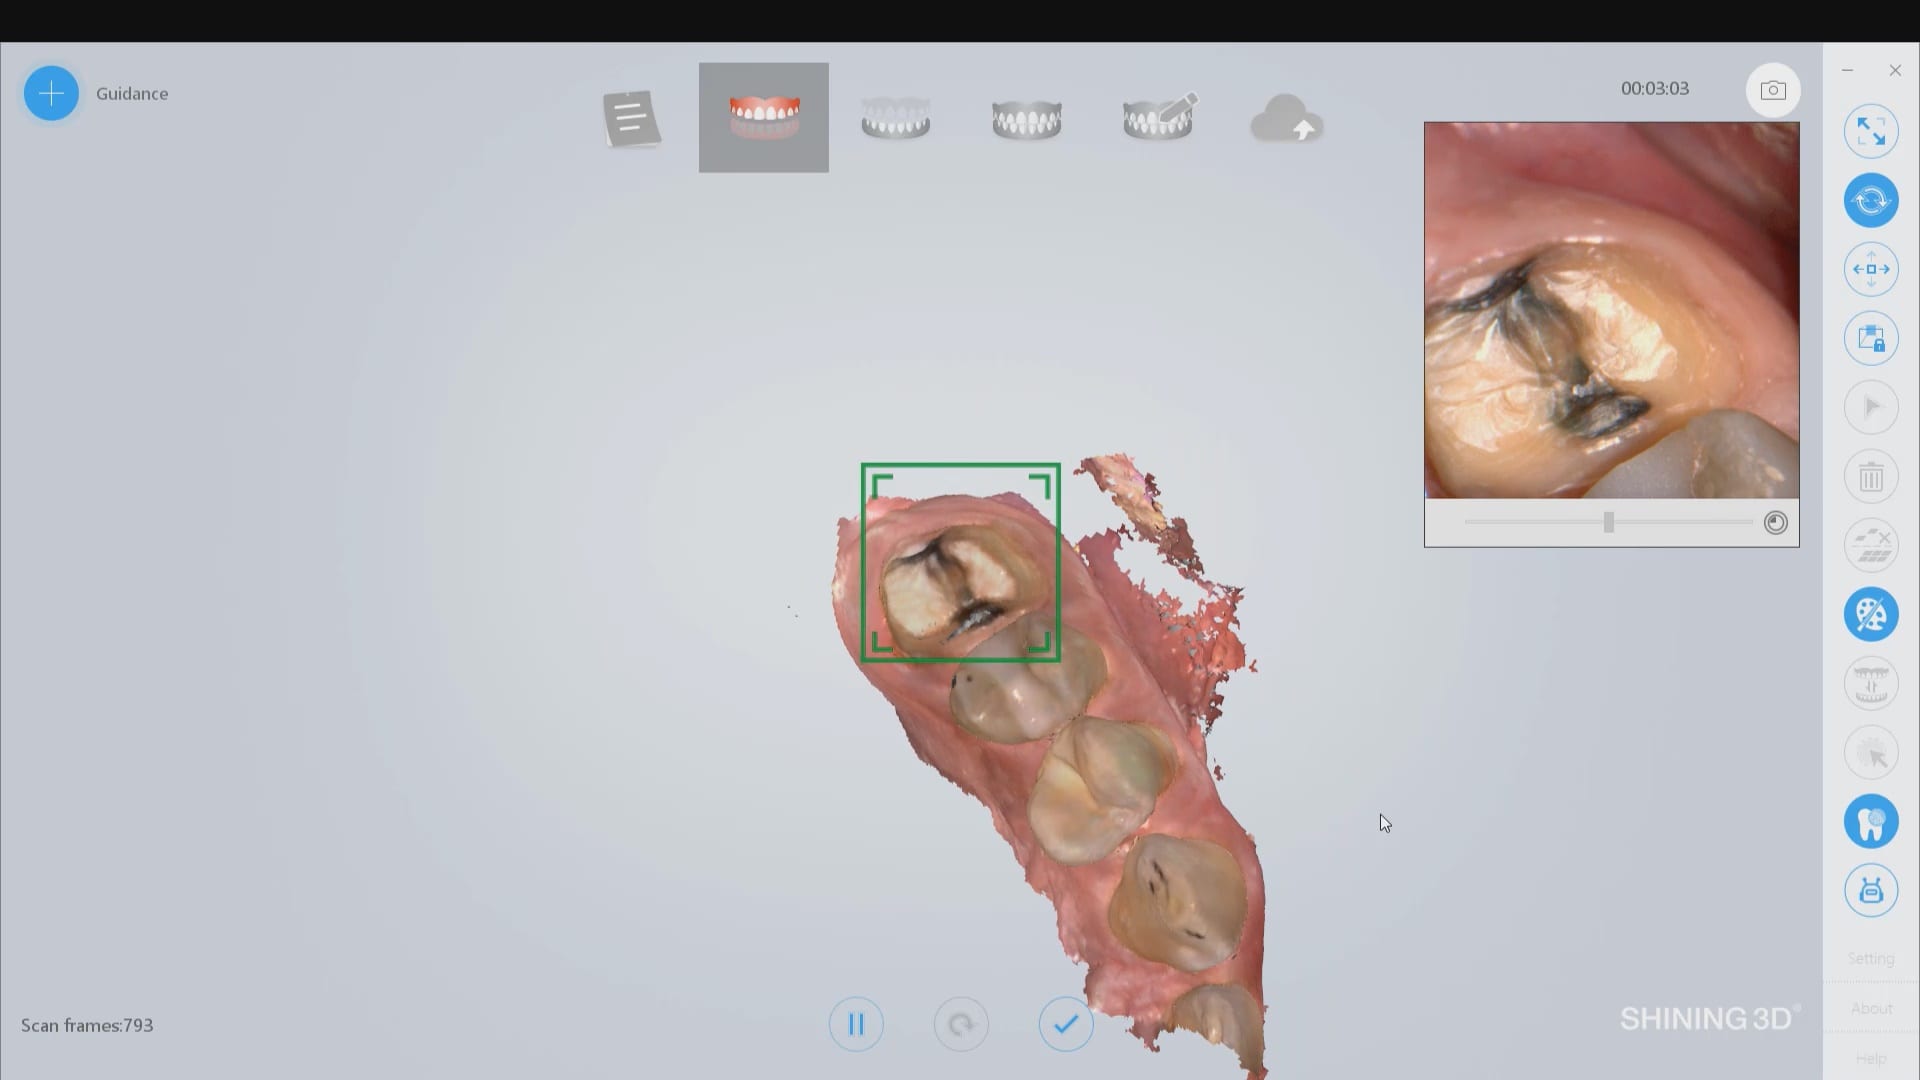

March 9, 2020Most manufacturers recommend that you start your imaging at the second molar area, which is the least practical area to start with. The tongue and the lip and saliva are […]